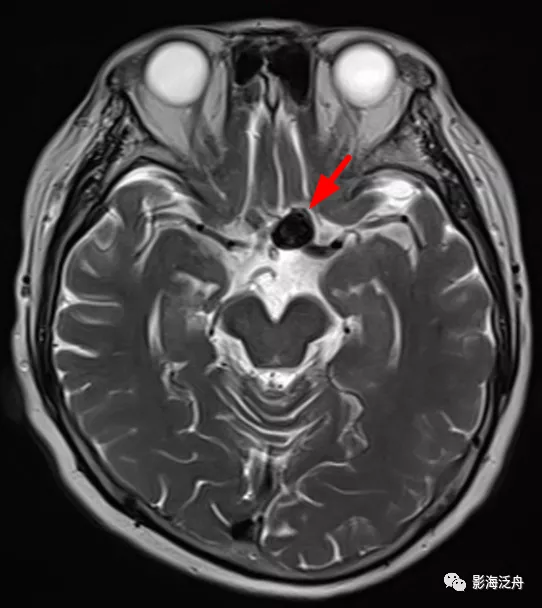

病例一:患者男,51歲,頭暈1月餘,神經系統查體無殊,血壓正常。

病例一:煙霧病。如圖所示,T2WI序列上在腦底池可以看到多發雜亂的細小流空血管影(紅箭頭),右側側裂池中大腦中動脈間斷顯示,且管腔粗細不均,而左側大腦中動脈完全不顯影(黃箭),兩側的大腦後動脈顯示清晰(綠箭頭)。腦底池中細小血管影增多的另一個常見原因多見於顱內感染,比如病毒性腦炎或隱球菌腦炎等。